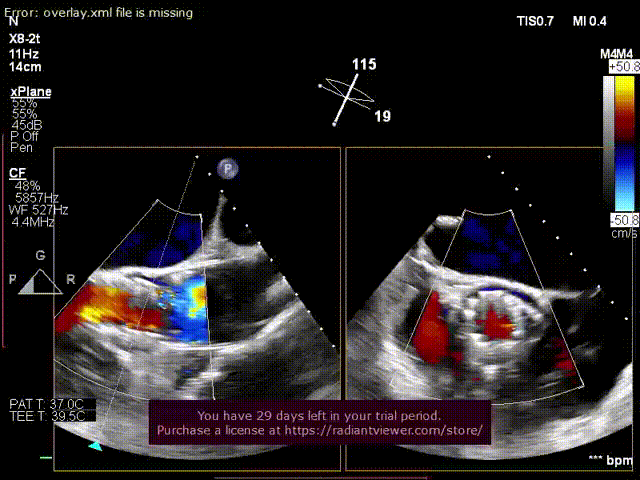

超声术后评估:

超声显示假体瓣膜形态良好,工作正常,少量瓣周漏。

超声显示假体瓣膜形态良好,工作正常,微量瓣周漏。